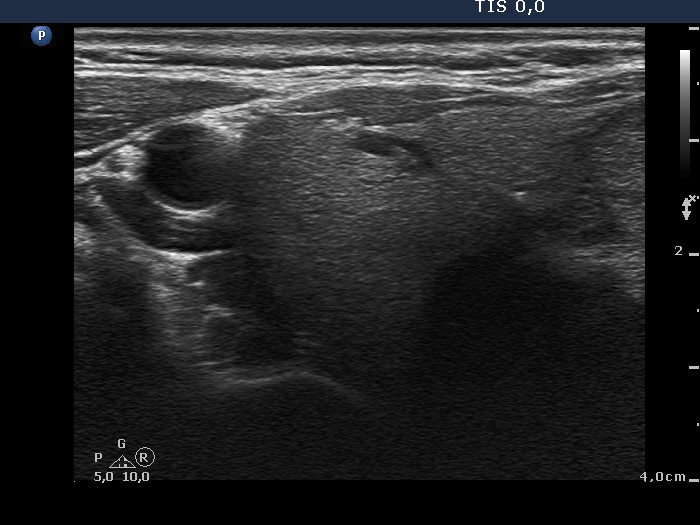

Ultrasonography. The thyroid was echonormal and presented several discrete hypoechogenic lesions. There was a large moderately hypoechogenic nodule in the isthmus. The nodule did not display halo but did perinodular blood flow.